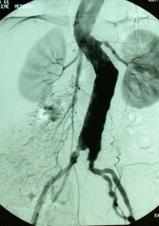

Additional diagnostic methods such as CT, MRI, and angiography may be used to plan treatment. These identify the size (the most critical factor in treatment), location, and relationships to surrounding organs. Angiography is not usually required for open surgery planning but is recommended for endovascular repair.

A less invasive option is to place a stent graft inside the vessel through catheters, known as endovascular aneurysm repair (EVAR). This method has a 10-year history. It is done without opening the abdomen, using small incisions in the groin under X-ray guidance.

In this method, the artificial graft is inflated at the aneurysm site and fixed internally with hooks. Patients are usually discharged in 1–2 days. However, this method is not suitable for all cases. The aneurysm may continue to enlarge or rupture even after the graft is placed, so periodic CT or Doppler ultrasound follow-up is necessary. Unlike open surgery, EVAR may not provide permanent cure.